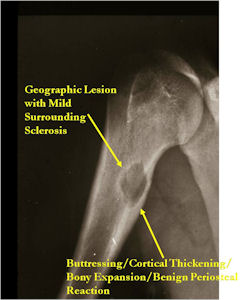

- Geographic, circumscribed lesion usually around 5cm in size.

- There may be expansion of bone, cortical thinning and cortical breakthrough. A soft tissue mass may accompany this lesion but the soft tissue component is usually contained by the periosteum.

- The periosteum remains intact around the soft tissue component. Might need a CT scan to detect the subtle calcification (Egg Shell Rim of Calcification) associated with an intact periosteal reaction

- The lesion may be entirely radiolucent but usually shows some degree of mineralization. Mineralization may appear stippled like cartilage but do not see chondroid pathologically. Mineralization is sometimes better detected on a CT scan rather than an x-ray.

- Usually less surrounding sclerosis than an osteoid osteoma.

- Most have a similar radiographic appearance as a conventional osteoblastoma and have well defined margins, variable amounts of mineralization and peritumoral sclerosis. They occasionally have radiographic characteristics consistent with malignancy.